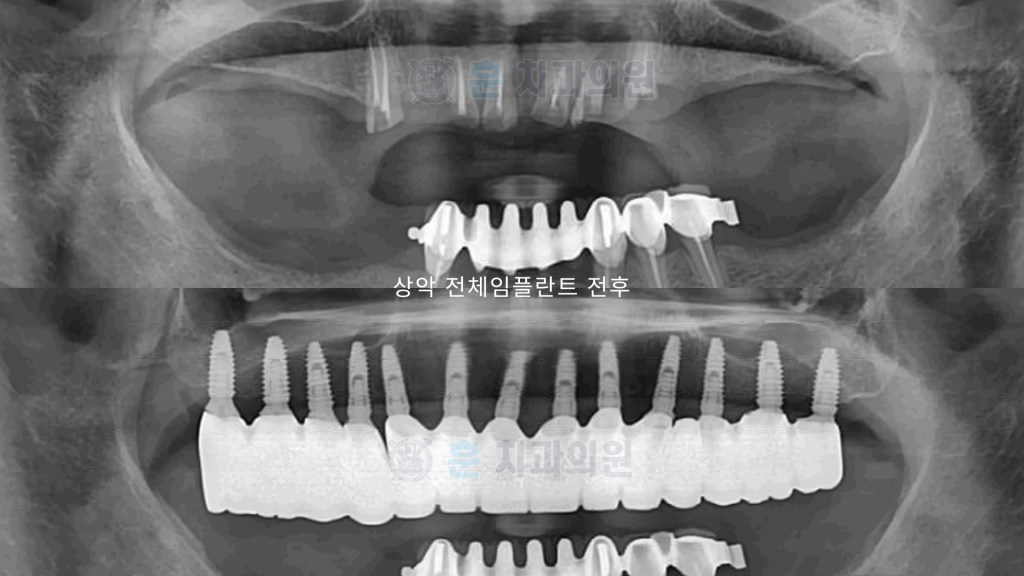

임플란트 8/10개 식립

맞춤 보철 12/14개 완성!

미아사거리 전체임플란트 전후

오랜 기간의 심한 치주염과 반복적 치아 파절로 통증·저작 장애가 심해진 환자분입니다. 보존 가능성을 충분히 평가한 뒤, 정밀 CT와 구강스캔을 바탕으로 상악 전체임플란트를 계획했습니다. 염증 치아를 단계적으로 정리하고 감염을 제어한 후 디지털 가이드로 안전하게 식립했습니다.

수술 과정에서 회복을 돕기 위해 자가혈/연어주사 등을 적용했고, 임시 보철로 적응 기간을 거친 뒤 최종 보철을 장착했습니다. 이후 정밀한 교합 조정으로 씹는 힘을 균형 있게 분산시켜 편안한 저작과 자연스러운 발음을 확보했습니다. 현재 환자분은 일상 식사가 한결 편해졌으며 심미적으로도 만족도가 높습니다. (개인 상태에 따라 계획·기간·결과는 달라질 수 있습니다.)